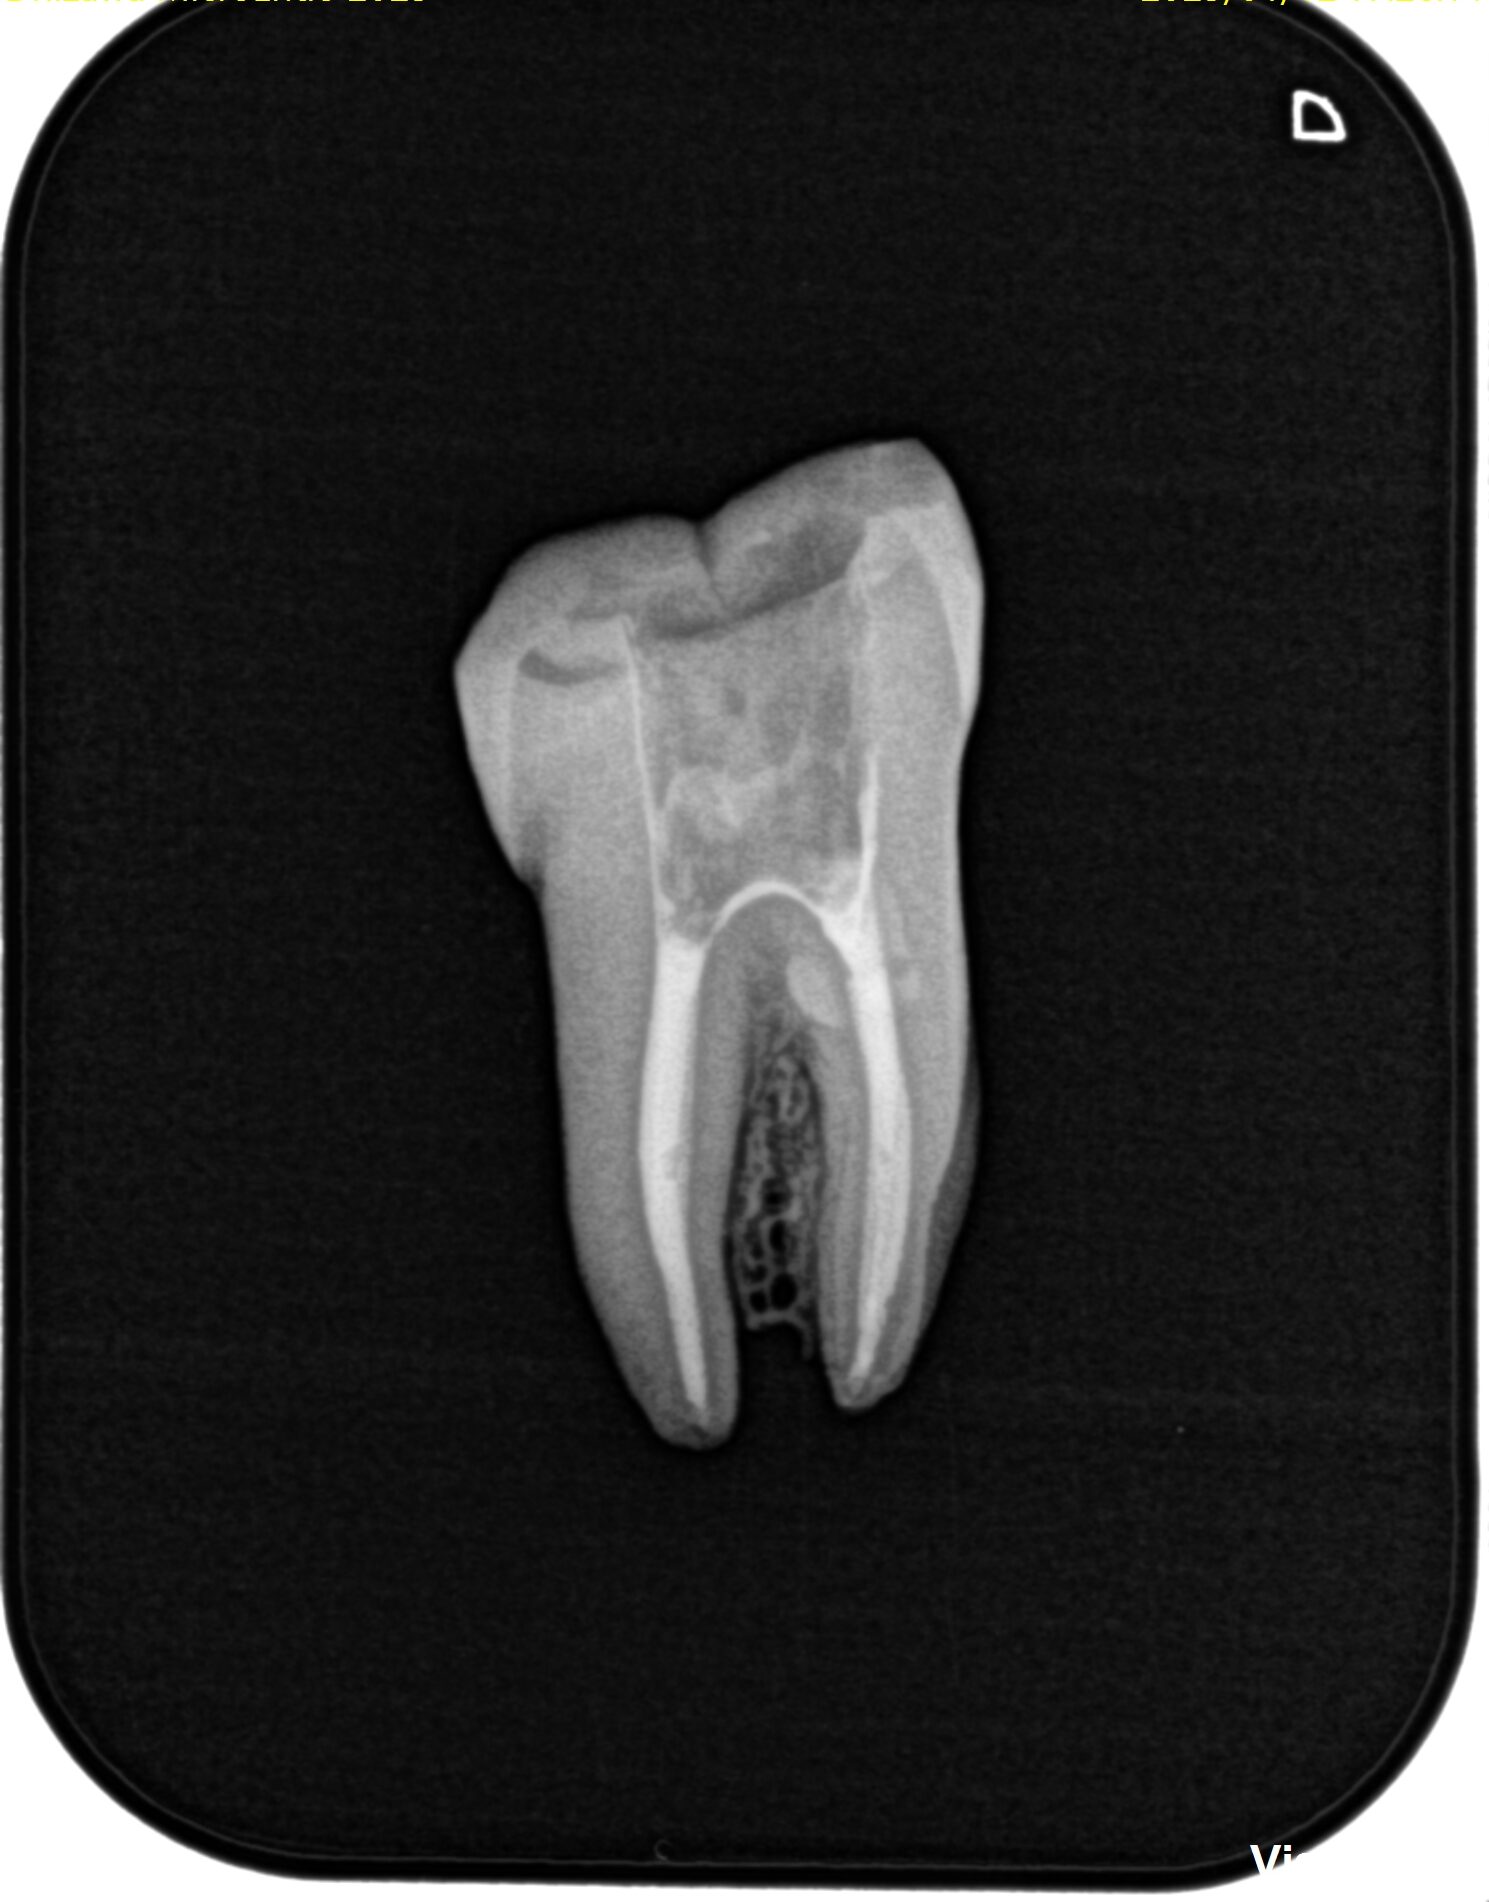

根管形成が終われば根管充填である。

これに関しては日本で購入できる道具で比較的安価に治療が行える方法を受講者には教授した。

そして根充のコツは以下を理解することである。

誤差があるもので形成し、誤差があるもので根充するのである。

現代の歯内療法は試適との戦いである